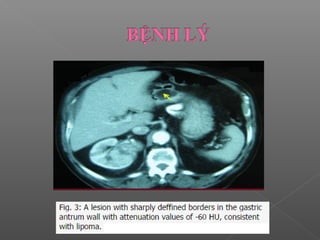

 Tổn thương khu trú lớp dưới niêm mạc

(Presentation as focal submucosal lesion):

 Dễ bỏ sót trên CT do kích thước nhỏ  cần phải

đánh giá kĩ.

 Tổn thương nằm hoàn toàn ở lớp dưới niêm mạc

 Hay gặp nhất là leiomyoma và lipomas

 Leiomiomas, lipomas, u bao dây thần kinh

U lành tính ít gặp

Lipomas: thấy thành phần mỡ của u

 Dễ bỏsót trên CT do kích thước nhỏ  cần phải đánh giá kĩ.  Tổn thương nằm hoàn toàn ở lớp dưới niêm mạc  Hay gặp nhất là leiomyoma và lipomas